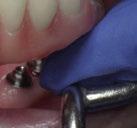

Ejecución técnica quirúrgica mediante férula guiada Bajo anestesia infiltrativa realizamos extracciones atraumáticas de todas las piezas a excepción de los dientes que actúan como anclaje o pilares para la fijación de la férula quirúrgica (Figuras 20 y 21). Seguidamente insertamos la férula comprobando una buena adaptabilidad y estabilidad

Figura Figura en posición ideal. Figura Figura

Figura

de dientes estratégicos para fijar la férula quirúrgica.

Figura 23. Férula quirúrgica inferior. Figura 24. Fresado guiado con férula y cucharilla. Figura 20. Extracciones dentales. 21. Conservación Figura 22. Férula quirúrgica superior. Figura 25. Inserción de implante RSX de Bego a través de férula quirúrgica. Figura 27. Conexión de pilar angulado multiplus sobre implante. Figura 26. Implante insertado en lecho a través de férula quirúrgica. Figura 28. Muestra del perfecto paralelismo tras la colocación de pilares angulados multiplus. Figura 29. ScanBody sobre pilares transepiteliales.

(Figuras 22 y 23). Se realiza fresado transgingival mínimamente invasivo y guiado hasta la inserción de los implantes, siguiendo el protocolo preestablecido e indicado (Figuras 24 a 26).

Durante la colocación de los implantes comprobamos una inserción con torque superior a 35 N/cm2

Retiramos la férula y comprobamos una correcta estabilidad primaria mediante mediación de valores

ISQ favorables en la mayoría de los implantes. Seguidamente se extraen los dientes remanentes que han actuado de medio retentivo para la férula quirúrgica.

Dentro de la fase quirúrgica propiamente dicha, una vez terminada la inserción de los implantes y

comprobada su estabilidad primaria, colocamos pilares transepiteliales

Multiplus para registrar una impresión digital mediante escaneado sobre ellos (Figuras 27 a 29)